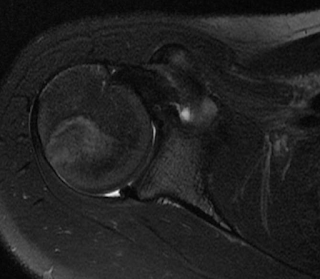

Below is a case of primary osteoarthritis of the shoulder with significant retroversion and a type C glenoid. The retroversion was to 60 degrees which was addressed with concentric reaming of the glenoid and implantation of an anterior eccentric head, as well as, closure of the rotator cuff interval.

There was 60 degrees of retroversion of the glenoid while the humeral head was posteriorly subluxated. As shown below the ration of AB/AC should be approximately 50% in order for the humeral head to "sit" in the center of the glenoid. In our case this ratio was 0%.